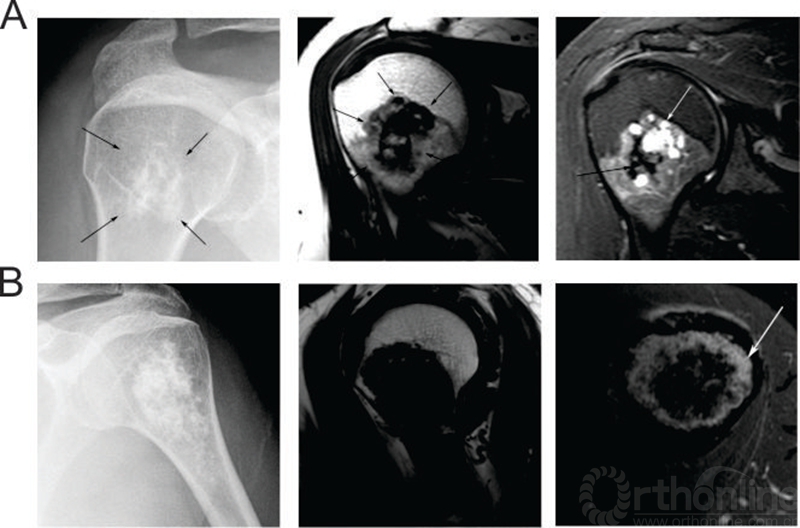

另外,MRI检查对软骨肉瘤的诊断也颇具价值,研究发现,病变在髓内占位大于病变部位的90%,高度提示软骨肉瘤,针对那些占位小于90%的病例,出现非连续性的软骨基质样改变或卫星样分布的软骨基质,高度提示软骨肉瘤[3]。即便如此,单纯通过影响学的表现包括MRI检查也很难以将低度恶性的软骨肉瘤和内生软骨瘤相鉴别,Crim[9]等的研究发现通过X片正确诊断(通过病理检查确认)内生软骨瘤的比例为67.2%,通过MRI正确诊断内生软骨瘤的比例为57.8%;通过X片正确诊断低度恶性软骨肉瘤的比例为20.8%,通过MRI正确诊断中度或高度恶性软骨肉瘤的比例为57.8%;通过平片和MRI正确诊断交界性病变的准确率分别为29.7%和28.1%。因此,对于那些影像学表现提示高度恶性(皮质破坏和软组织侵袭)的软骨肉瘤可以根据活检结果确定病变性质,而对那些低度恶性软骨肉瘤或者怀疑内生软骨瘤的病例在影像学指导下穿刺活检或者切除活检(尤其是长骨内的病变)是有必要的[5,10]。(图1[9])

图1:内生软骨瘤(A)与软骨肉瘤(B)的影像学表现